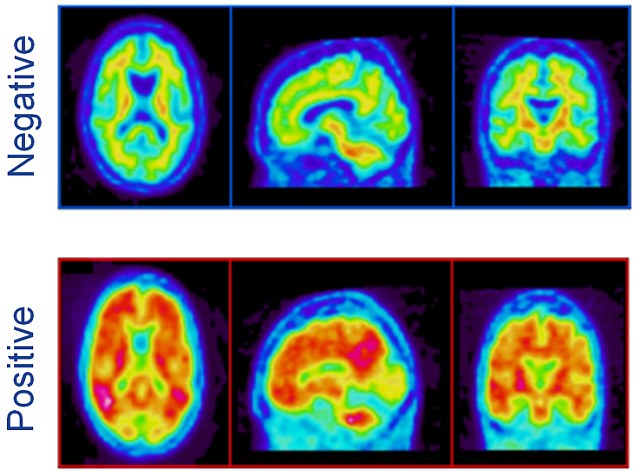

下圖一為健康的人的腦波掃描結果,下圖二則是罹患阿茲海默症的病患。

阿茲海默腦波掃描